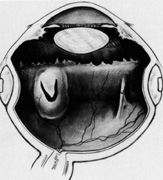

Current cryotherapy instrumentation employs expansion of high-pressure nitrous oxide at the tip of a probe generating temperatures as low as 89°C. The temperature effect is confined to the tip of the probe by an insulating sleeve. A probe 2.0 to 2.5 mm in diameter usually is used for retinal work. Treatment of retinal breaks and pathologic conditions requires accurate placement of the cryoprobe tip. The surgeon must be certain that the indentation visualized with the indirect ophthalmoscope is the tip of the probe and not the shaft. Confusion between the tip and the shaft of the cryo-probe can cause inadvertent posterior freezes.33 To minimize the possibility of this complication, the surgeon must indent only with the tip of the cryoprobe (Fig. 10). It is also helpful to perform the first freezes at the most anterior aspect of the area requiring treatment to assess both location and intensity of treatment.

Fig. 10. A. Inadvertent posterior placement of cryoprobe tip caused by visualization of cryoprobe shaft. B. Correct placement of cryoprobe tip.